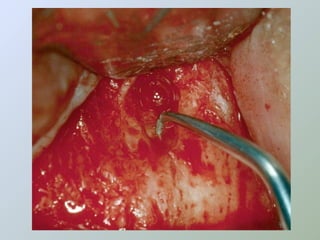

Ressecção do

ápice radicular

- apicectomia -

apicectomia

• Acesso ao canal para

exame e inserção de

material obturador

• Para remover uma porção

não debridada/obturada

da raiz

• Dilacerações radiculares

• Obstruções nos canais

• Acessos às estruturas

linguais/palatinas

• Antes da apicectomia, devemos

expor e isolar o ápice

• Apicectomia com angulação

adequada

• Remover uma quantidade

suficiente para expor canais

colaterais

A amputação do ápice radicular deve ser

feita com broca montada em baixa rotação,

com abundante irrigação.

A angulação da broca em relação ao longo eixo

dental deverá ser de 90°, removendo-se desta

maneira o delta apical completamente (BERNARDINELLI

et al. 1994; BRAMANTE; CLÓVIS MARZOLA,BERBERT, 2000 e

MARZOLA, 2000 e 2002),

apesar de ainda alguns autores

serem adeptos da inclinação para vestibular

(SAILER; PAJAROLA, 2000).